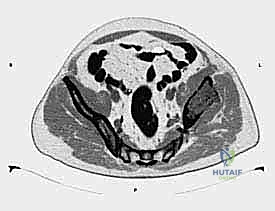

- التصوير المقطعي المحوسب (CT Scan): يقدم صوراً ثلاثية الأبعاد تُظهر بدقة متناهية مدى تدمير القشرة العظمية، وهو الفحص الأهم للتخطيط الجراحي وتحديد خطر حدوث الكسور المرضية.

- التصوير بالرنين المغناطيسي (MRI): الفحص الأفضل لتقييم امتداد الورم خارج العظم إلى الأنسجة الرخوة (العضلات، الأوعية الدموية، الأعصاب) وتقييم مدى إصابة نخاع العظم.

- الخزعة (Biopsy): في حال كان الورم في الحوض هو أول ظهور للسرطان (سرطان أولي مجهول المصدر)، يتم أخذ عينة من الأنسجة تحت إرشاد الأشعة المقطعية لتحديد نوع الخلايا السرطانية بدقة.